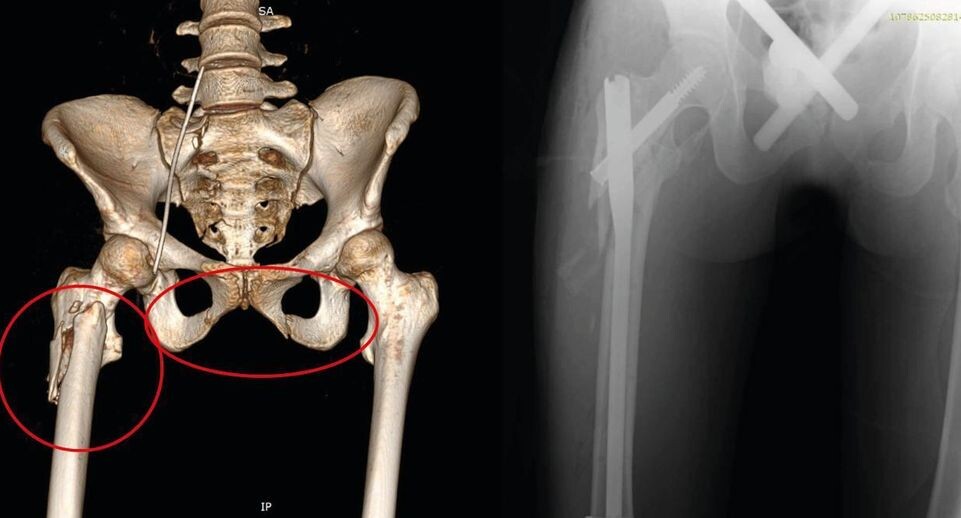

Врачи провели диагностику и выявили повреждения головы, легких, травмы живота и грудной клетки, а также переломы костей таза и бедра.

Специалисты также установили специальные аппараты внешней фиксации на таз и бедро пациентки, которые сняли на 20-й день.

В сознание она пришла на пятый день, а уже на восьмой ее состояние стабилизировалось, после чего врачи зафиксировали титановым штифтом сломанную бедренную кость девушки.